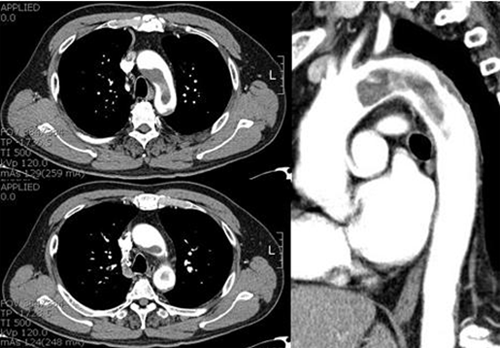

A 65 year-old man was visited out patient clinic for regular check up. Although he had a history of percutaneous coronary intervention due to old myocardial infarction 16 years ago, he had no experience of angina or other cardiovascular symptom for follow-up duration. He was a ten pack-year ex-smoker, his lipid profile was poorly controlled. The resting electrocardiogram disclosed normal sinus rhythm without any pathologic findings. The transthoracic echocardiographic examination (TTE) showed preserved systolic function and no valvular abnormality despite of old posterior wall hypokinesia. In the routine view of suprasternal notch, we found a mass-like lesion and abnormal eccentric jet in aortic arch. Subsequently, a transesophageal echocardiography (TEE) was performed for evaluation of the thoracic aorta, revealing a 3 x10 cm sized hypermobile pedunculated cylindrical mass in the aortic arch (Fig. 1). Its margin was smooth, internal contour was homogeneous comparatively. It appeared to attach to the posterior wall of the proximal aortic arch and to extend into the left subclavian artery and the descending aorta. Computer tomography confirmed the presence of the mass seen in TEE (Fig. 2). The entire thoracic aorta had normal dimensions with some visible atheromatous plaques.

¡ã Figure 2. Computed tomographic images shows a huge floating thrombus in the aortic arch.